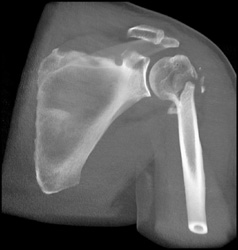

Humerus Fracture